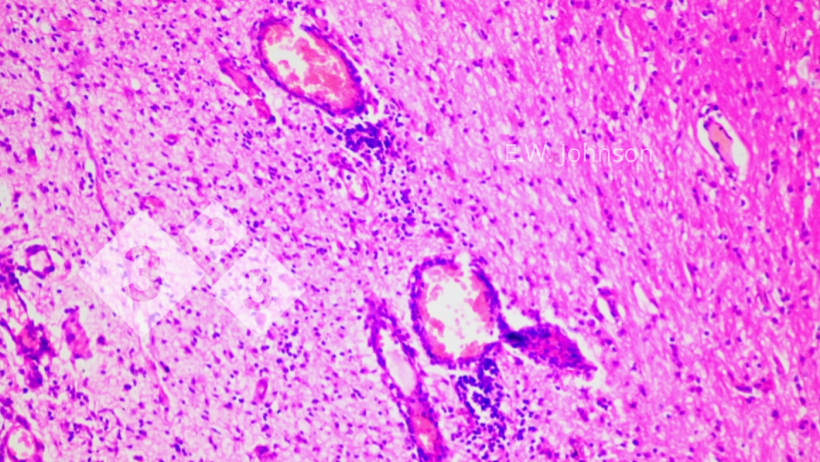

Imagem 2. Manguitos perivasculares e gliose. Cérebro.

O exame microscópico do cérebro revela meningoencefalite com algemas perivasculares e gliose (imagem 2) e infiltração das meninges com células inflamatórias mononucleares e polimorfonucleares mistas (imagem 3). Imagem 3. Meningite com células mononucleares e algumas células polimorfonucleares. Cérebro.